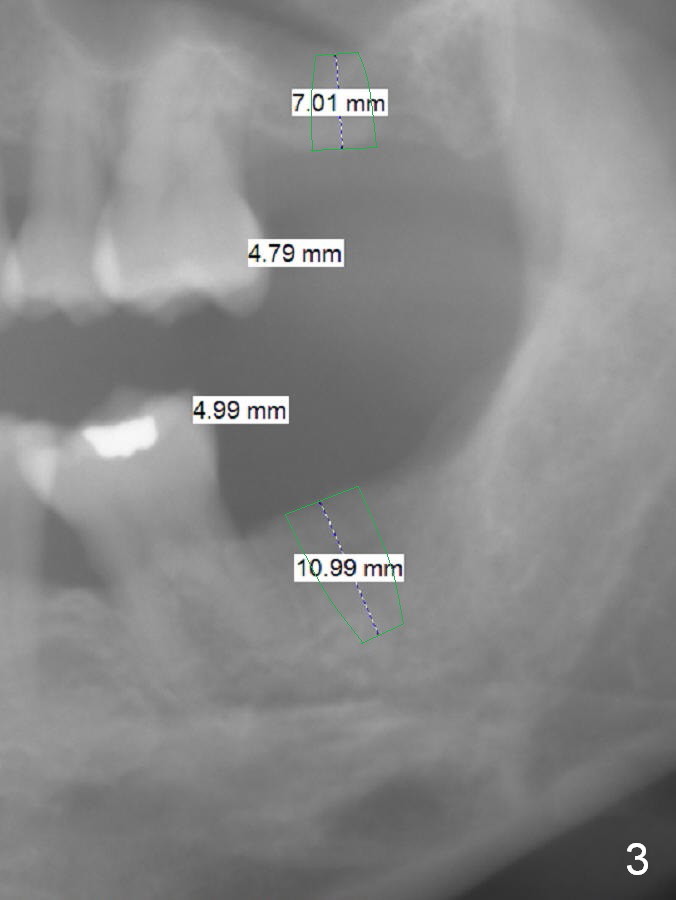

A 32-year-old woman is concerned about her upper anterior tooth flaring (Fig.1). She is eager for periodontal treatment. She masticates on the right side. The teeth #15 and 18 were extracted ~ 1 year ago. To lessen anterior flaring (take photos when she returns), implants are going to be placed at these sites (Fig.2,3). IBS and Magic Sinus Lift Kits will be used for #15. Magic Split gains access for 5 mm deep (gingival level), followed by ME 3 mm and next ME for 5 mm and Sinus lifter for 9 mm (bone level 7 mm, CMC). Or use the 4.3 mm drill from Magic Sinus Lift Kit for 5 mm, followed by Sinus Lifter for 9 mm. Insert PRF plugs into the sinus, followed by allograft (.5-1.0 mm) with Osteogen. If implant stability is low, place a healing abutment or screw.

For #18 implant placement, palpate the ridge to determine the width. Trim the ridge if it is pointed. Also use Magic split for access and bone density testing. Either BEB or PBR will be adopted.